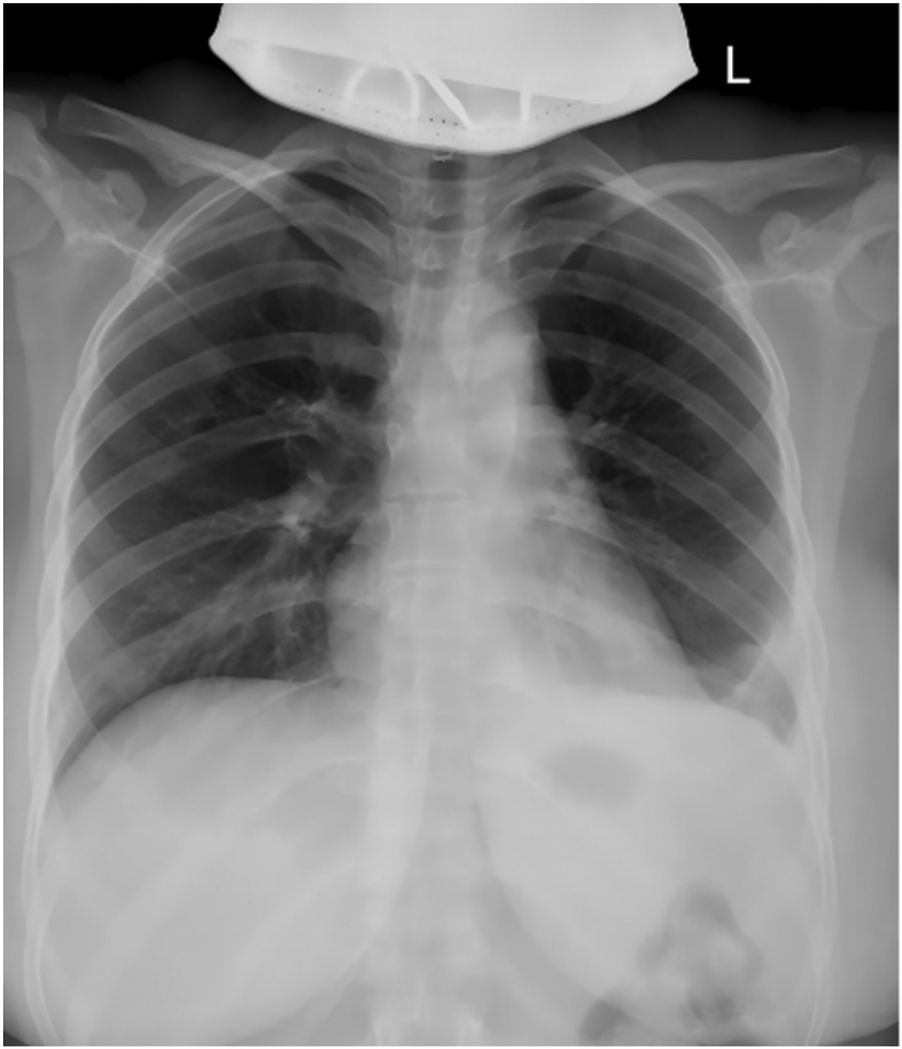

After completing the necessary laboratory tests and confirming the absence of surgical contraindications, the patient underwent “artificial pneumothorax, thoracoscopic resection of the anterior mediastinal tumor via a left thoracic approach, extended thymectomy, and closed chest drainage” under general anesthesia. The procedure involved a 1.5 cm incision at the left mid-axillary line in the 5th intercostal space for a 12 mm thoracoscopic port, with additional operating ports placed at the 5th and 2nd intercostal spaces along the left midclavicular line. After inducing artificial pneumothorax, a cystic lesion measuring 6.5 × 5.0 × 4.5 cm was identified in the anterior mediastinum, partially adhering to the left upper lobe (Figure 2A). Upon opening the cyst wall, brown fluid was released (Figure 2B). The cyst, along with adipose tissue anterior to the pericardium and the retrosternal anterior mediastinum in front of the brachiocephalic vein, was carefully dissected (Figure 2C), and the specimen was retrieved in a bag (Figure 2D). Intraoperative frozen section analysis confirmed the lesion to be a benign cystic structure, and the operation proceeded without complications. Final pathology, along with IHC staining (SYN+, CK7+, CK20–, MUC-5ac–), confirmed the diagnosis of a mediastinal pancreatic pseudocyst (Figures 3A–D). Postoperatively, the patient showed good recovery. A follow-up chest x-ray indicated improvement in the left lung exudative lesion compared to prior images, and her condition remained favorable (Figure 4). The patient was discharged with the diagnosis of “anterior mediastinal cyst (mediastinal pancreatic pseudocyst)”.